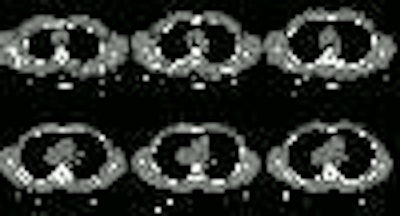

A CT scan confirmed the presence of bilateral hilar and mediastinal adenopathy. The patient was presumed to have sarcoid, but had a negative biopsy and was subsequently found to have histoplasmosis. (Click on small image to view larger radiograph)